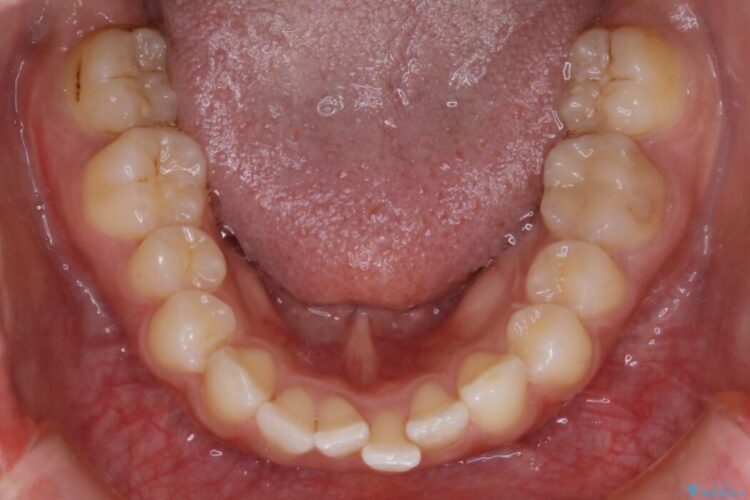

気になるガタツキと噛み合わせを改善したいとご来院されました。

下の歯列よりも上の歯列が前に出ている状態を治すため、マウスピース矯正に加え、患者様にゴムかけのご協力をいただきました。その結果、ガタつきが改善し、上下の噛み合わせが適切な位置で合うようになりました。